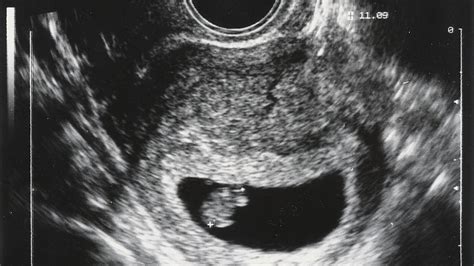

Erste Ultraschalluntersuchung

Zwischen der 9. und 12. SSW erfolgt die erste große Ultraschalluntersuchung. Hierbei werden Lage und Länge des Kindes ermittelt. Schwere Fehlbildungen können bereits ausgeschlossen werden.